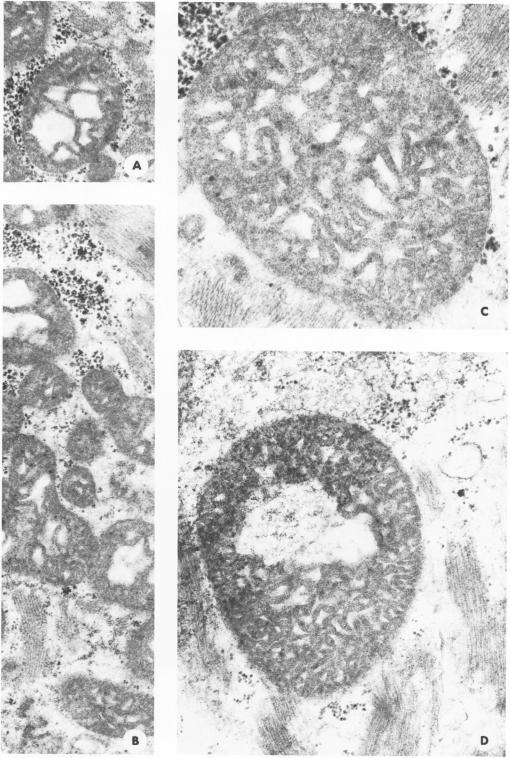

Skeletal muscle samples from the upper and lower extremities of 38 human fetuses (6 to 18 weeks' gestation) of both sexes were studied by histologic, histochemical, and electron microscopic methods. Ultrastructural morphometry was applied. In the different stages of normal development are found regressive changes, ranging from reversible dystrophic to irreversible necrotic alterations, which are characteristic of either primary myogenic myopathies or primary neurogenic muscle atrophies in older age. Several pathologic patterns of so-called congenital myopathies also presented. On the basis of their findings, the authors conclude that in a certain group of congenital myopathies full normal development of muscle is hindered or blocked and that groups of muscles or the whole voluntary musculature is arrested at certain stages of maturation. For example, insufficient or absent innervation of the fetal muscle may be a factor in Werdnig-Hoffmann or Kugelberg-Welander syndromes. The authors' findings suggest that pathologic patterns in muscle diseases have been used physiologically in fetal development to eliminate unnecessary overproduction of muscle fibers.

采用组织学、组织化学和电子显微镜方法,对38例不同性别的人类胎儿(妊娠6至18周)上下肢的骨骼肌样本进行了研究。应用了超微结构形态测量法。在正常发育的不同阶段发现了退行性变化,范围从可逆性营养不良到不可逆性坏死改变,这些变化是老年原发性肌源性肌病或原发性神经源性肌肉萎缩的特征。还呈现出几种所谓先天性肌病的病理模式。基于他们的发现,作者得出结论,在某一组先天性肌病中,肌肉的完全正常发育受到阻碍或阻断,并且肌肉群或整个随意肌在成熟的某些阶段停滞。例如,胎儿肌肉的神经支配不足或缺乏可能是韦尔纳格 - 霍夫曼或库格尔贝格 - 韦兰德综合征的一个因素。作者的发现表明,肌肉疾病中的病理模式在胎儿发育过程中已被生理利用,以消除不必要的肌纤维过度产生。